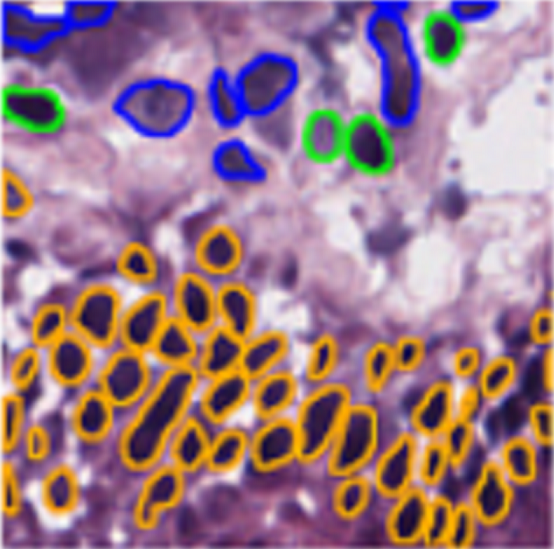

However, nuclei and glands instance segmentation cannot be regarded as a simple task for non experts in pathology labs. Despite being continuous advancements in learning algorithm, nuclei segmentation is still an extremely challenging task because of blurred nuclei boundaries, differences in size and shape highlighted by Vahadane et al. [12], uneven staining, pathological changes on pathological images, morphological abnormalities [13] and substantial color variations described by Rashmi et al. [14]. Similarly, varying morphology of glands at different histological grades, different intrinsic features of glands WSIs poses major challenge during segmentation of instances. Firstly, applying mathematical shape model for instance segmentation gets difficult due to shapes heterogeneity. Figure 2 shows structural variations of nuclei in different organs. Secondly granule filled cytoplasm cause nucleus extrusion to flat shapes as compared to oval or round structures in normal cases mentioned by Yan et al. [15]. Thirdly, cellular matrix variations results in anisochromasia thus resulting in additive noise in background compared to normal intensity gradients.

3.1.1 CoNSeP

CoNSeP (Colorectal Nuclear Segmentation and Phenotypes Dataset) is one of the first fully annotated open source dataset that enabled the development of models for simultaneous nuclear segmentation and classification approaches in Computational Pathology. It consists of 41 Haematoxylin and Eosin (H&E) images of size 1,000×1,000 px from colorectal adenocarcinoma (CRA) Whole slide images (WSIs) [26].

3.1.5 Lizard

Lizard [29] (A Large-Scale Dataset for Colonic Nuclear Instance Segmentation and Classification) is the largest known dataset available for nuclei segmentation and classification in digital pathology having nearly half a million annotated nuclei along with their class label, consists of whole slide image regions of colon tissue having six different dataset sources including GlaS, CRAG, CoNSeP, Digest Path, PanNuke and TCGA at 20× magnification. Its fully annotated dataset for about 495,179 nuclei. In particular we provide the nuclear class label for epithelial cells, connective tissue cells, lymphocytes, plasma cells, neutrophils and eosinophils.